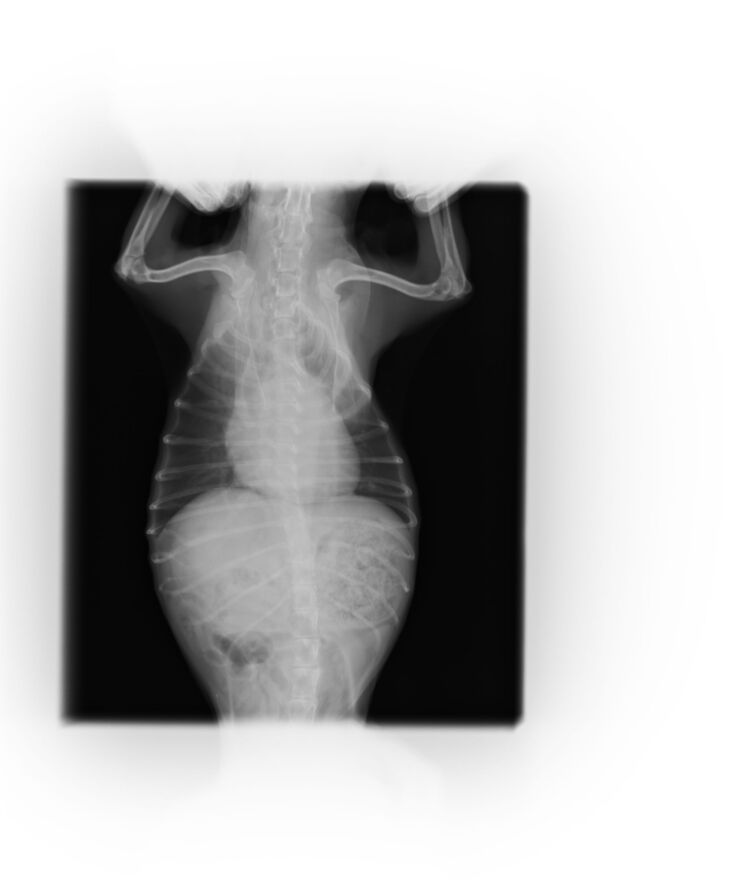

ーーーーー以下参考資料ーーーー

現在通院している病院の物です。

以下レントゲン写真